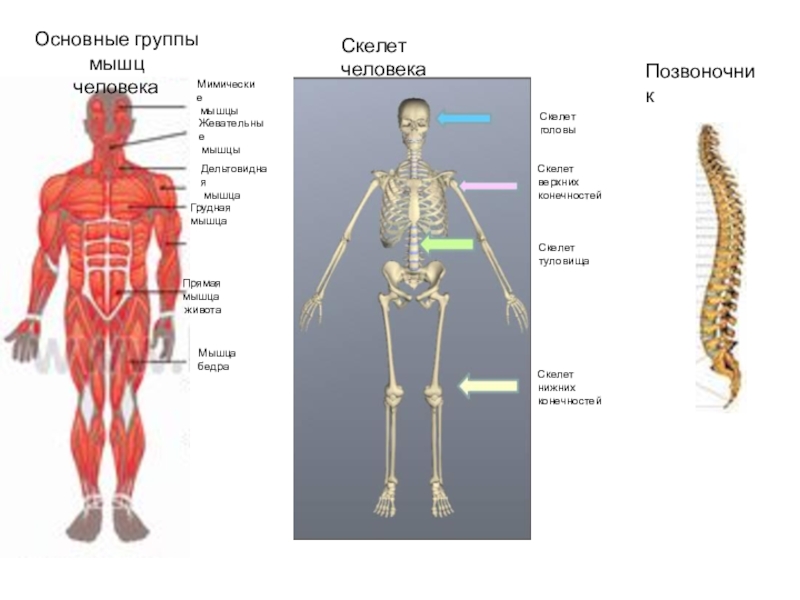

Анатомия человека: кровеносная система и её связь со скелетом